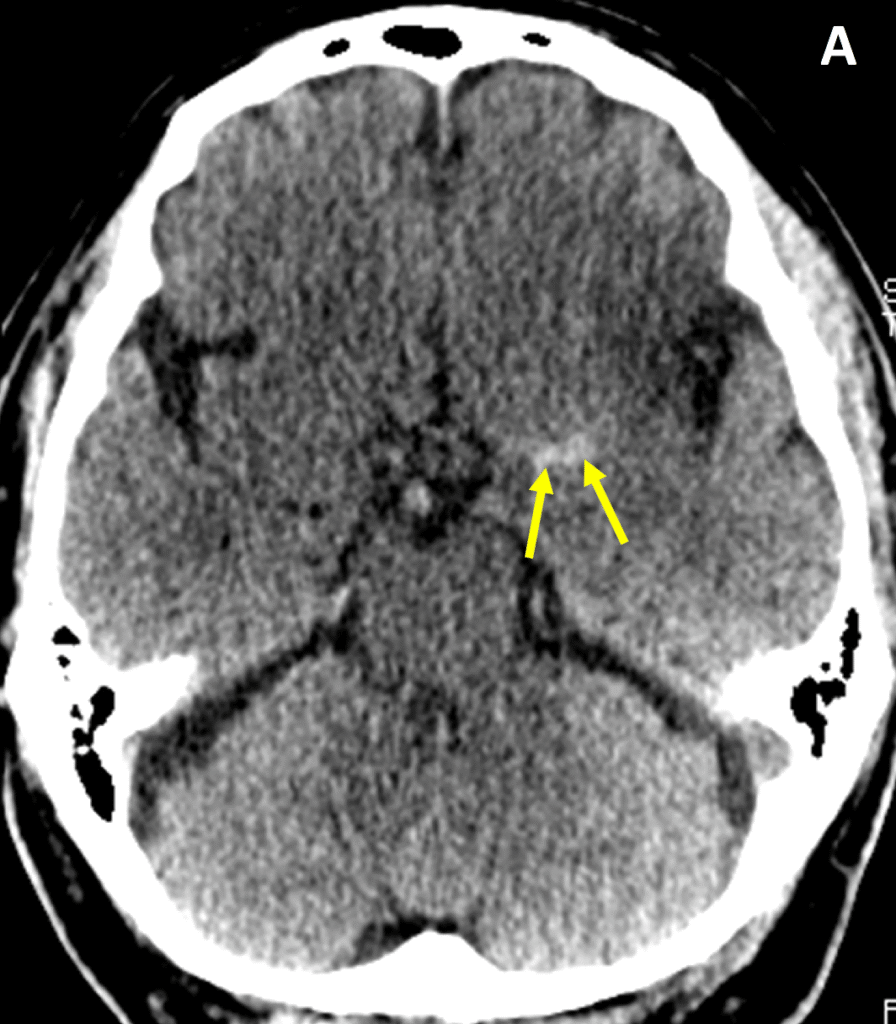

TC de crânio sem contraste, em corte axial, evidenciando sinal da artéria cerebral média hiperdensa (setas), achado sugestivo de trombo intraluminal e oclusão arterial aguda, compatível com AVC isquêmico em fase muito precoce.

Entre 3 e 6 h, começam a surgir os sinais isquêmicos precoces. O mais clássico é o apagamento da ínsula, a chamada “insular ribbon”. A ínsula perde sua diferenciação normal porque a substância cinzenta começa a se igualar à branca. Também pode ocorrer o obscurecimento do núcleo lentiforme, que normalmente é um pouco mais hiperdenso. Aqui começa a perda da diferenciação córtico-subcortical.

TC de crânio sem contraste, em corte axial, evidenciando obscurecimento do núcleo lentiforme (seta), com perda da diferenciação em relação ao hemisfério contralateral preservado, achado clássico de isquemia cerebral precoce em território da artéria cerebral média.